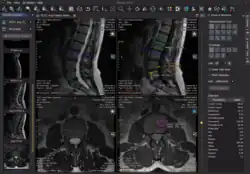

Weasis is an open source DICOM viewing software[2][3][4] for the visualization and analysis of medical images.

DICOM (Digital Imaging and Communications in Medicine) is the standard used to store and transmit medical imaging information. Weasis allows healthcare professionals to view and analyze these images for clinical purposes. It integrates with healthcare systems such as picture archiving and communication systems, radiological information systems, and electronic health records.

Weasis supports a range of DICOM file types, including multi-frame and enhanced formats. It integrates tools for fundamental image manipulation,[9][18] including panning, zooming, rotation, window level adjustment, filtering, and navigation through image series. Furthermore, it provides functionalities for linear, area and angular measurements on medical images.

For advanced image rendering, Weasis incorporates multiplanar reconstruction of CT scans[19] to generate reformatted planar views in any desired orientation, and maximum intensity projection to enhance the visualization of structures with high attenuation values. Additionally, volume rendering capabilities enable three-dimensional visualization.